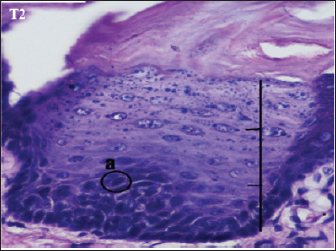

Fig. 4. Histopathological description of the rat tongue epithelium in the T2 group, microscope at ×400. (a) Variations in cell shape with hyperchromatic nuclei.